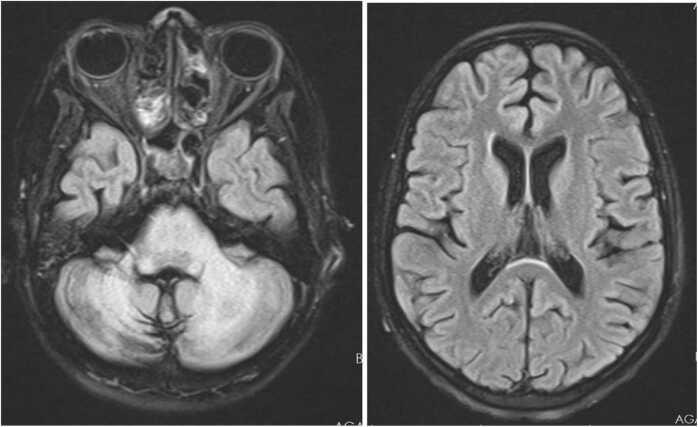

Progressive Multifocal Leukoencephalopathy (PML), primarily affecting immunocompromised individuals due to the John Cunningham virus (JC), is common in HIV-positive adults but rare in paediatrics. We present a unique case of a 14-year-old female with PML as the initial manifestation of HIV, with MRI lesions isolated to the posterior fossa. Initial symptoms included fever and rash, progressing to neurological deficits and ataxia. Severe immune suppression due to HIV and JC virus in the cerebrospinal fluid were confirmed. Management included immune reconstitution therapy (antiretroviral treatment) and supportive care. Despite interventions, the patient had a slow recovery with significant residual neurological sequelae. Timely recognition of Immune Reconstitution Inflammatory Syndrome (IRIS) and steroid initiation proved helpful. Antiretroviral therapy improved the survival rate of HIV-related PML, but long-term neurological sequelae, especially in posterior fossa cases, significantly impact the patient's quality of life. This case highlights diagnostic and treatment challenges in paediatric PML, particularly with atypical lesions location.

进行性多灶性白质脑病(PML)主要由约翰·坎宁安病毒(JC)感染引起,多见于免疫功能低下的个体,在HIV阳性成年人中较为常见,但在儿科患者中较为罕见。我们报告了一例独特的病例,一名14岁女性,以PML作为HIV的首发表现,MRI病变仅局限于后颅窝。初始症状包括发热和皮疹,随后进展为神经功能缺损和共济失调。脑脊液中因HIV和JC病毒导致的严重免疫抑制得到证实。治疗包括免疫重建治疗(抗逆转录病毒治疗)和支持治疗。尽管采取了干预措施,患者恢复缓慢,仍遗留明显的神经后遗症。及时识别免疫重建炎症综合征(IRIS)并开始使用类固醇治疗被证明是有帮助的。抗逆转录病毒疗法提高了HIV相关PML的生存率,但长期的神经后遗症,尤其是后颅窝病例,会显著影响患者的生活质量。该病例突出了儿科PML诊断和治疗中的挑战,特别是在病变位置不典型的情况下。